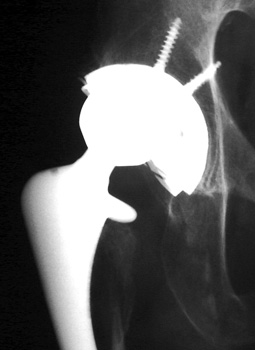

Severe polyethylene liner wear with associated osteolysis of ischium and proximal femur